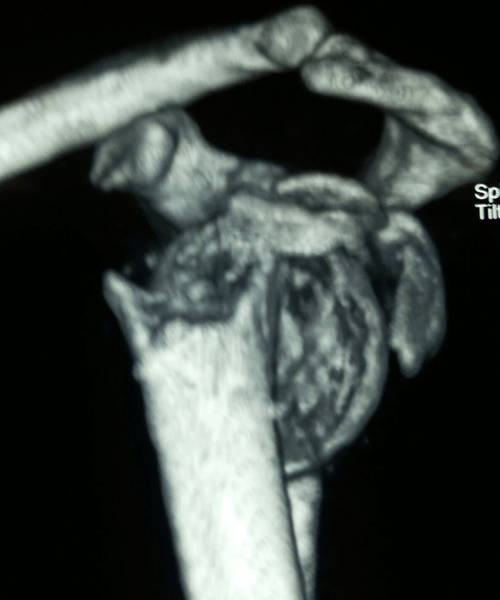

Case:18 Comminuted Fracture Upper Humerus

Female 65 years sustained fall in the house had displaced fracture of head of left Humerus with displaced fragment of greater tuberosity was treated with open deduction and philos plate fixation.

Pre-Op-Xray

Pre-Op CT Scan

CT Scan lateral